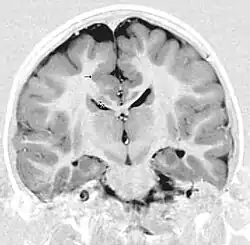

- Radiological findings (MRI) demonstrated symmetric generalized polymicrogyria with decreasing anterior-posterior gradient, most prominent in frontoparietal cortex.[5]

- Numerous gyrus on the cortex

- Small gyri and sulci

- Thin cortex

There are different tests or methods used to determine GPR56 expression or visuals of the brain to analyze the specific sections that are affected. These tests for example, using animals such as mice, RNAi, Behavioral assay, Electron microscopy, CT scan, or MRI demonstrate different results that concludes an affected BFPP patient.[15] MRI's reveal either irregularity to the cortical surface suggestive of multiple small folds or an irregular, scalloped appearance of the gray matter-white matter junction.

Neuroimaging

The diagnosis of polymicrogyria is typically made by magnetic resonance imaging (MRI) since computed tomography (CT) and other imaging methods generally do not have high enough resolution or adequate contrast to identify the small folds that define the condition. The cerebral cortex often appears abnormally thick as well because the multiple small gyri are fused, infolded, and superimposed in appearance.[5]

Gross neuropathologic examination reveals a pattern of complex convolutions to the cerebral cortex, with miniature gyri fused and superimposed together, often resulting in an irregular brain surface. The cortical ribbon can appear excessively thick as a result of the infolding and fusion of multiple small gyri.[5]

Microscopic examination demonstrates that the cerebral cortex is in fact abnormally thin and has abnormal lamination; typically the cortex is unlayered or has four layers, in contrast to the normal six layers. The most superficial layers between adjacent small gyri appear fused, with the pia (layer of the meninges) bridging across multiple gyri. Prenatal diagnosis for BFPP is also available for pregnancies at risk if the GPR56 mutations have been identified in an affected family member.[5]